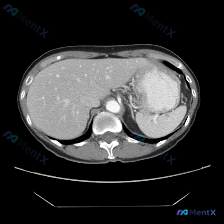

先整理一下这份病例的核心影像表现

- 肝脏:形态尚可,实质密度未见明显异常局灶性减低或增高区

- 脾脏:左上腹,形态及大小未见明显增大,实质密度均匀,边界清晰,与周围脂肪组织界限分明

- 胃:胃底及胃体可见,管腔内有内容物(高密度影),胃壁未见明显局限性增厚

- 胰腺尾部:周围脂肪间隙尚清晰,未见明显肿块或渗出

- 血管、淋巴结、腹膜腔:腹主动脉、门静脉走行清晰;腹膜后未见明显肿大淋巴结;腹水好发部位未见液性暗区

- 整体印象:从本张横断面图像观察,未见明显的腹部实质脏器占位性病变、肝硬化征象、明显腹水或腹膜后淋巴结肿大